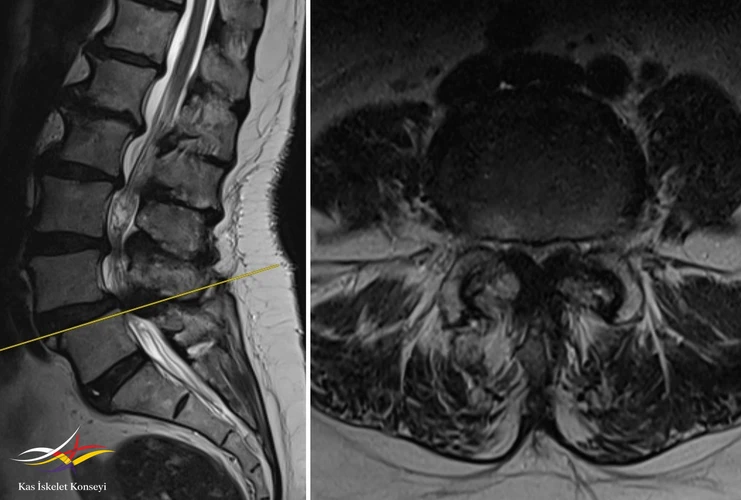

Resim 1. 2029 yılına ait suboptimal MRG de L4-5 listezis ve dar kanal görülmekte.

Resim 3. Lomber MRG'de L2-3 seviyesinde ılımlı bir darlık görülmekte.